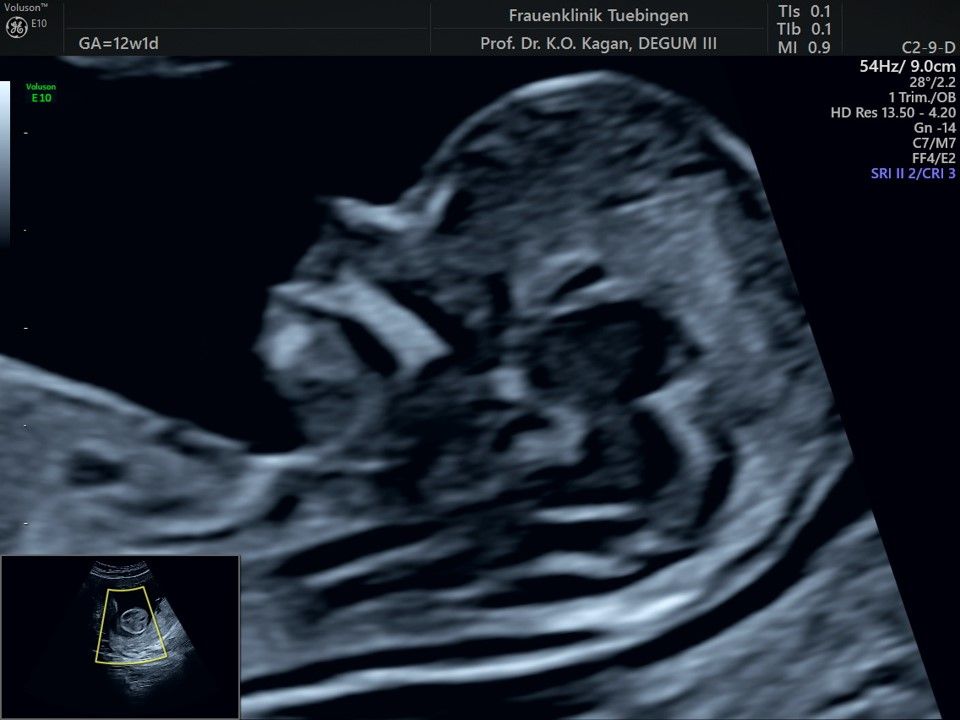

Im Rahmen des Ersttrimester-Screenings untersuchen wir die Organe des Feten mittels Ultraschall. Dabei machen wir auch gerne ein Bild für Sie.

Obwohl der Fet zu diesem Zeitpunkt erst zwischen 5 und 8cm groß ist, lassen sich bereits etwa die Hälfte aller schwerwiegenden Fehlbildungen erkennen bzw. ausschließen. Sollten wir eine Auffälligkeit sehen, werden wir mit Ihnen den Befund und das weitere Vorgehen ausführlich besprechen.

Die eigentliche Organuntersuchung findet um die 20.SSW (zweites Screening) statt. Das Ersttrimester-Screening und das zweite Screening sind sich ergänzende Untersuchungen und ersetzen sich gegenseitig nicht.

Herz